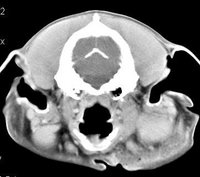

imágenes de TC en el perro | ||||||||||

ejemplo de imágenes de TC en el perro. Nótese la celulitis en la región parotídea izquierda | ||||||||||